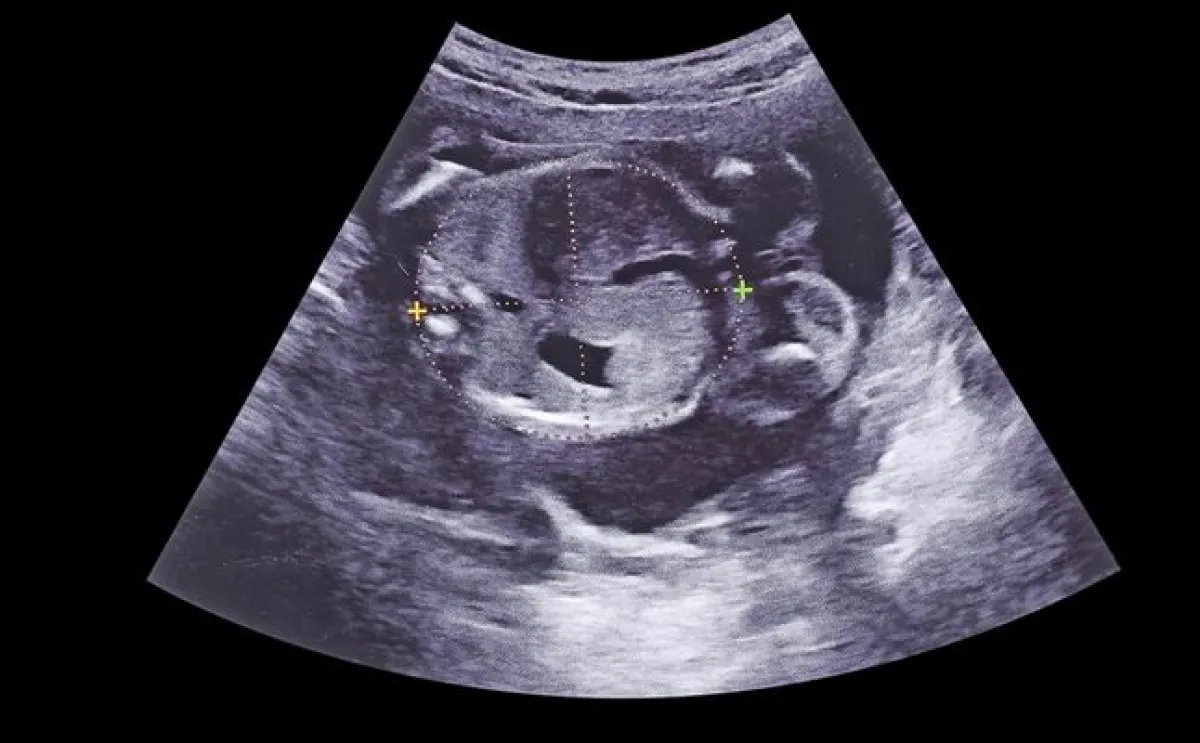

يتطور كثيراً نمو الجنين خلال كل شهر ويزداد حجم بطن الأم وذلك مع ازدياد حجم ووزن الجنين، فكيف يكون شكل الجنين خلال الشهر الخامس من الحمل، وهو الأسبوع الثامن عشر، يبلغ طول الجنين خلال الشهر الخامس من الحمل نحو 14 سنتيمتراً، أما وزنه فيبلغ نحو 141 غراماً، قد تشعر الحامل خلال هذا الأسبوع بتحرك الجنين وركلاته حول الرحم، كما تستطيع الحامل أن ترى الجنين وهو يتثاءب خلال خضوعها لفحص بالموجات فوق الصوتية، إضافة إلى ذلك، يتطور خلال هذا الأسبوع الجهاز المناعي عند الجنين.